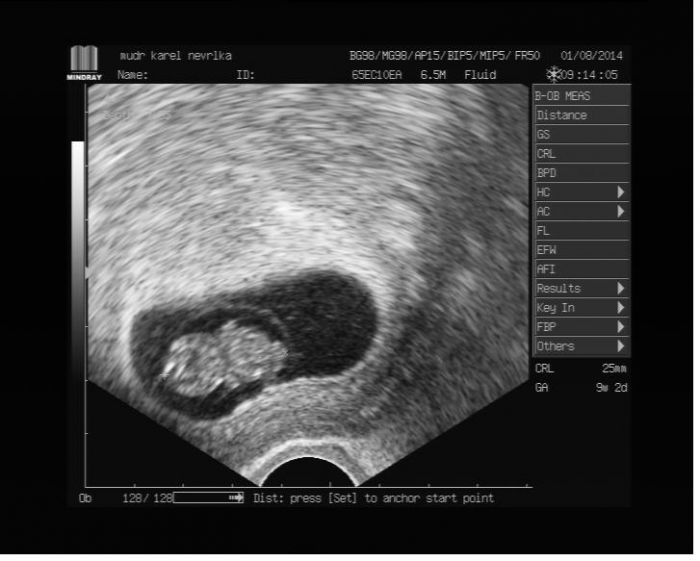

Ahoj holky, taky bych se k vám ráda připojila. Jsem dneska 8 + 3. Čekám první miminko. Na kontrolu jdu taky v pátek, ale já chodím častěji, protože jsem v minulých týdnech trochu zakrvácela a zašpinila. Prý je to kvůli tomu, že se mi v děloze vytvořil malý hematom. Doufám, že už to bude všechno dobrý